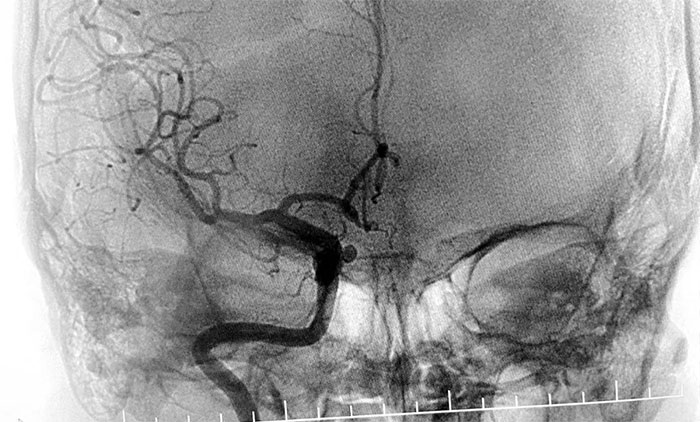

患者入院后,余志良主任为患者完善查体,根据病情特点,着重排查脑血管疾病可能。通过CTA检查,发现右侧颈内动脉C6段动脉瘤。医院学术副院长、神经内科4A病区主任席刚明教授团队进一步行DSA脑血管造影检查,提示右颈内动脉眼动脉段动脉瘤。

▲ DSA检查提示,右颈内动脉眼动脉段动脉瘤